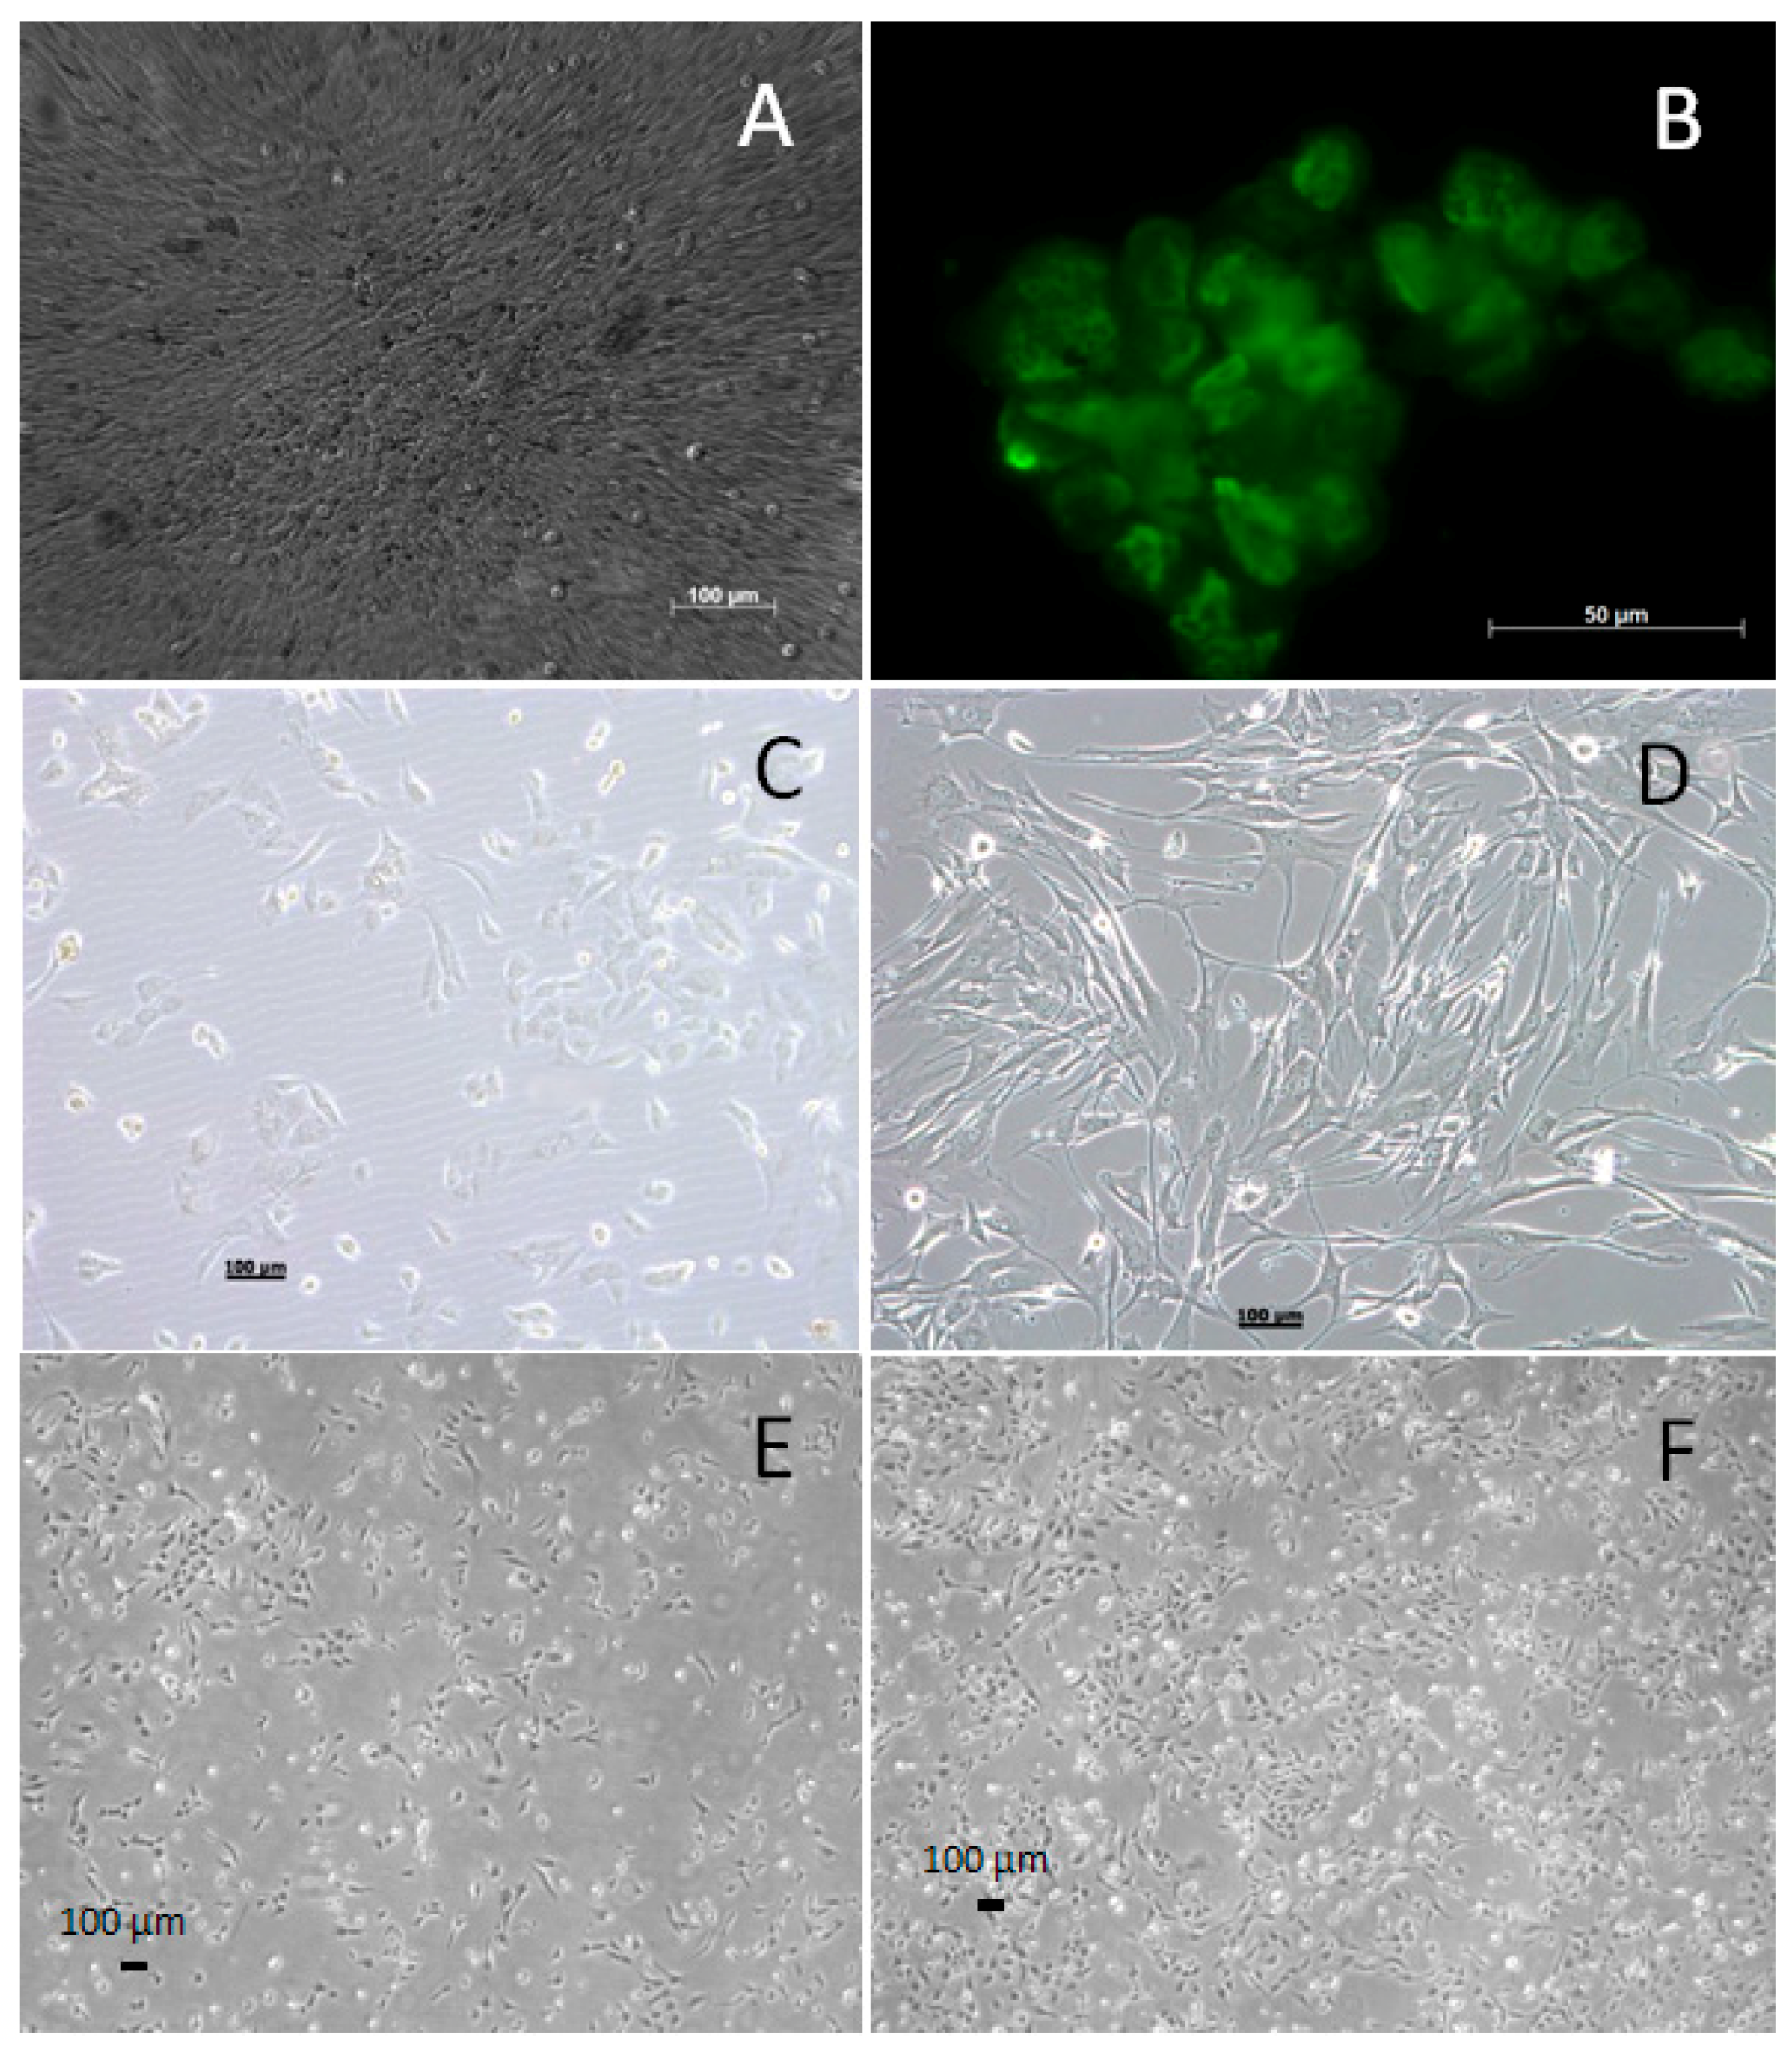

3.1. Generating and Characterizing the WG-59 Cell Line

3.2. Cytogenic Characteristics and DNA Profile of the WG-59 Cell Line

3.3. Flow Cytometry Analysis of the WG-59 Cell Line